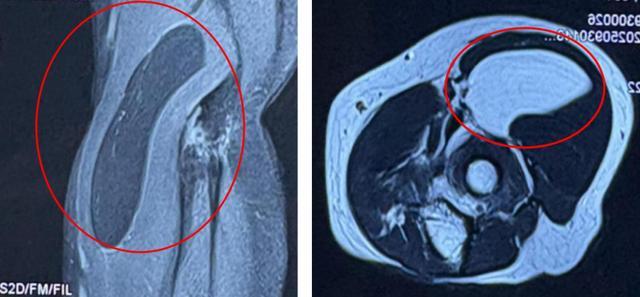

MRI结果示:右肘关节周围肌间隙内含脂肪信号占位,性质待定,才发现罪魁祸首是右肘前方的较大脂肪瘤。这个看似无害的“肉疙瘩”,已经压迫到了正中神经,影响了手部的神经功能,从而引发了手部的麻木、无力等症状。

(▲MRI结果显示:右肘关节周围肌间隙内含脂肪信号占位,性质待定)

术中,医师将右肱桡肌向外侧牵开,暴露出右肘前方约8×3厘米大小黄色质软包块,果然,肿块与正中神经紧密相连。医师团队仔细游离,小心翼翼保护好正中神经,最终,将这个大的脂肪瘤完整地剥离下来。